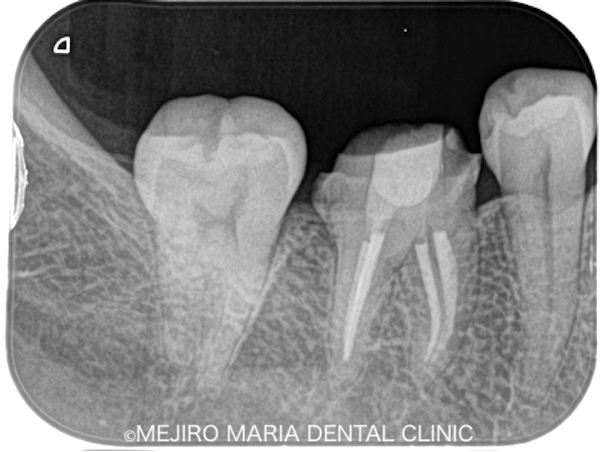

|治療前画像3-1.png)

患者様は、右下の奥歯が痛いことを主訴に来院されました。右側の歯で食べ物を噛むと、鋭く強い痛みがあるとのことです。

右下6番の歯には、金属の詰め物(インレー)が装着されていましたが、レントゲンならびに視診での診査では、虫歯を確認することはできませんでした。また、歯髄の生活反応(※)も正常であることから、一部分補綴(インレー)を除去し、う蝕(虫歯)の確認を行いましたが、金属の下にも虫歯は確認できず、処置後も痛みに変化は見られませんでした。

そこで当院では「クラックシンドローム」を疑い、特別な方法を用いて診査を行いました。

「クラックシンドローム」とは、歯ぎしりや食いしばりなどにより歯に亀裂が入り、咬合時にひび割れが広がることによって、歯髄に知覚過敏のような痛みを誘発するものです。通常の歯髄診査などでは、原因となる歯の特定が困難なため、特殊な器具を使い診査・診断を行うことが求められます。